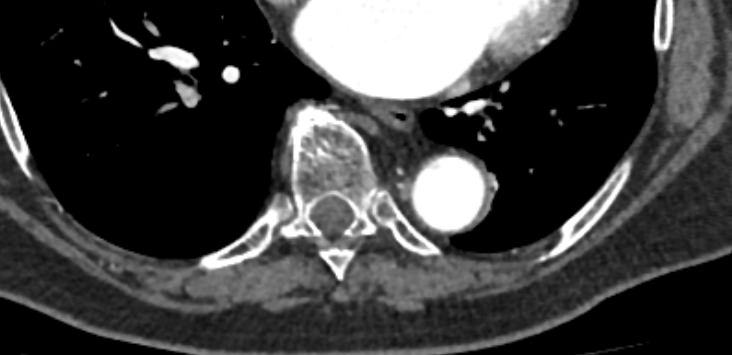

Грудная аорта делится на несколько отделов – восходящий отдел аорты, дуга аорты и нисходящий отдел. Корень аорты отходит непосредственно от левого желудочка, в его состав входят синусы Вальсальвы от которых берут начало коронарные артерии. После корня, прослеживается тубулярная часть восходящего отдела аорты, которая переходит в дугу аорты.

Дуга аорты дает начало брахиоцефальным артериям, которые питают головной мозг и верхние конечности. Затем следует нисходящий отдел аорты, распространяющийся через отверстие в диафрагме. От грудного отдела аорты отходят висцеральные артерии, кровоснабжающие органы средостения: бронхиальные, пищеводные, перикардиальные, медиастинальные артерии.

При истончении стенки аорты или ее ветвей формируется аневризматическое расширение участка сосуда, которое долгое время может никак себя не проявлять. Симптомы часто появляются при развитии осложнений – расслоения аневризмы (при разрыве внутренней оболочки сосуда и возникновения внутристеночной гематомы), разрыве аневризмы. Эти угрожающие жизни состояния можно избежать при своевременном выявлении аневризмы и проведения хирургического лечения.

Одним из информативных методов диагностики сосудистой патологии является мультиспиральная компьютерная томография грудной аорты и ее ветвей (КТ-ангиография). Метод сканирования при помощи рентгеновских лучей и цифровой обработки данных позволяет получать послойные снимки сосудов и трехмерные реконструкции сосудистой системы в мельчайших подробностях.

Для того, чтобы качественно визуализировать сосудистую систему КТ-ангиография предусматривает в обязательном порядке применение контрастного усиления. Йодсодержащее контрастное вещество вводится пациенту внутривенно и, благодаря способности контраста поглощать рентгеновские лучи, ярко контрастирует сосудистую систему на фоне окружающих тканей.

КТ-ангиография позволяет диагностировать аневризмы аорты, сосудистые аномалии развития, воспалительные изменения стенок сосудов, пристеночные тромбы, сужения просвета сосудов за счет сдавления извне близлежащими опухолевыми образованиями.